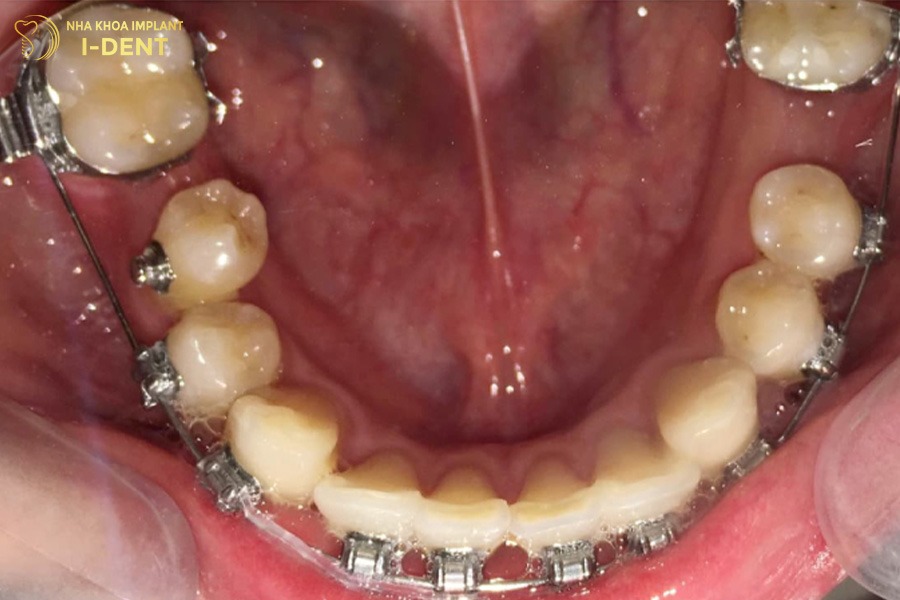

- Răng số 7 và răng số 8 vẫn còn: Đây là điều kiện lý tưởng để tiến hành niềng răng mất răng số 6. Bác sĩ sẽ tiến hành lắp các khí cụ niềng để kéo chỉnh 2 chiếc răng này vào khoảng trống. Sau khi quá trình điều trị hoàn tất, răng số 7 sẽ thay thế vị trí và vai trò của răng số 6 còn răng khôn sẽ trở thành răng số 7.

- Niềng răng mắc cài: Đây là phương pháp niềng răng truyền thống, sử dụng lực tác động của mắc cài cùng dây cung để kéo chỉnh răng số 7, số 8 vào vị trí răng số 6 để lại. Mắc cài có nhiều loại khác nhau như mắc cài kim loại bền chắc, mắc cài tự động điều chỉnh răng với tốc độ nhanh hoặc mắc cài sứ mang đến sự thẩm mỹ. Giá niềng răng mắc cài có chi phí thấp hơn các phương pháp chỉnh nha khác nên được nhiều bệnh nhân lựa chọn để khắc phục tình trạng mất răng số 6.

Niềng răng mất răng số 6

Niềng răng trong suốt Invisalign diễn ra đơn giản vì mỗi khay niềng đều được sản xuất và đánh thứ tự sẵn, bạn chỉ cần đeo và thay khay định kỳ theo đúng yêu cầu của bác sĩ. Trong khi đó, với phương pháp niềng răng kim loại và niềng răng sứ, bác sĩ sẽ gắn mắc cài lên thân răng bằng composite, sau đó luồn dây cung vào rãnh mắc cài rồi cố định lại bằng dây thun.

Bác sĩ đang tiến hành niềng răng mất răng số 6 cho bệnh nhân